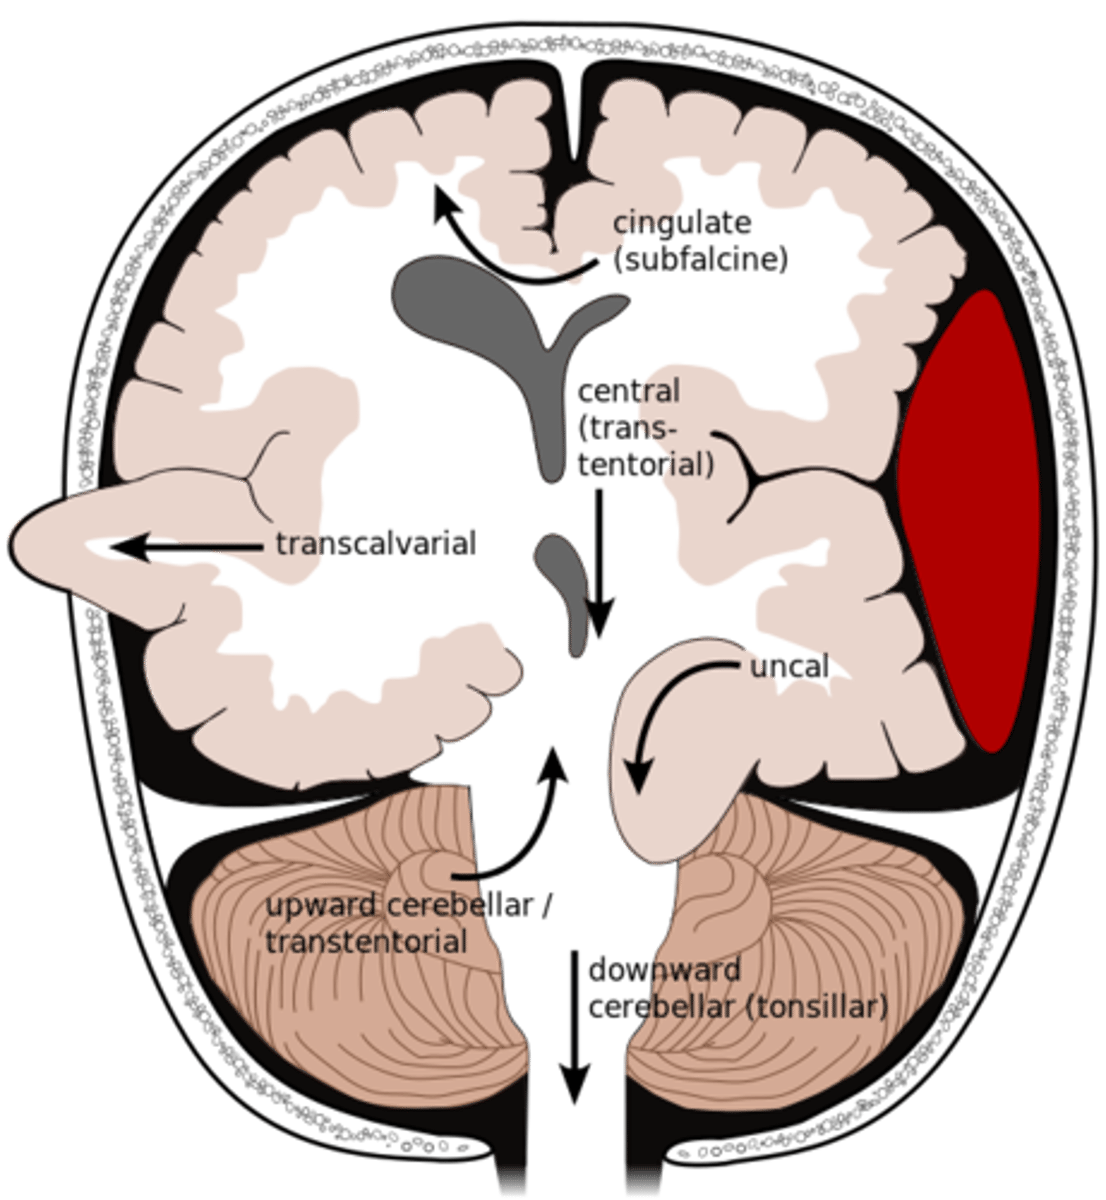

What is an uncal herniation?

most common.

unilateral lesions forces uncus of temporal lobe to displace and compress on the midbrain.

What is a central herniation?

Downward shift of cerebral hemisphere, compressing the brainstem

What is a cingulate herniation?

shift of brain tissue from one hemisphere to the other. Compress anterior cerebral artery.

Ischemic stroke may occur

What is a transcalvarian herniation?

brain begins to herniate outside of the skull. the brain will squeeze out of fractures, burr holes, or surgical incisions.

What is an upward herniation?

displacement of the cerebellum upward

What is a cerebellar Tonsillar herniation?

displacement of cerebellar tonsils downward this compressing the pons/medulla

s/s: alterations in resp. and cardiac functions- rapidly progressing to cardiac arrest, Headache and neck stiffness, reduced muscle tone